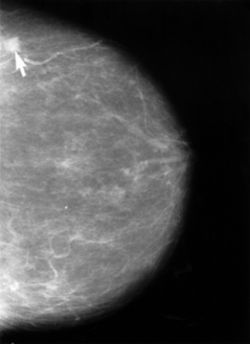

2024年の8月13日、梅宮アンナさんは乳がん(浸潤性小葉がん)ステージ3Aであることを公表されました。多くのファンが驚きと心配の声を上げたこの告白は、彼女自身も勇気が必要だったことでしょう。しかし、彼女は力強くその挑戦を受け入れ、前進することを決意しました。

11月には大胆にも彼女は右胸の全摘手術を選択しました。この選択は簡単なものではなく、身体的な負担だけでなく精神的な影響も考慮しなければならなかったはずです。それでも、彼女は未来を切り開くためにこの決断をしました。その後、年明けから抗がん剤治療が始まりました。抗がん剤治療は体力を大きく奪うもので、多くの患者が強い副作用と向き合わなければなりません。しかし、彼女はその治療を乗り越えました。

続いて、4月には放射線治療が始まりました。これは、乳がん治療において重要な工程の一つです。放射線治療は、局所的にがん細胞を攻撃することで、再発のリスクを減らす役割を果たします。梅宮さんは、この治療法についても前向きに取り組み、まさに「三大治療」をすべて完走しました。

2024年8月13日、彼女は乳がん、具体的には浸潤性小葉がんのステージ3Aであることを公表しました。

11月には右胸の全摘手術を受け、年が明けてからは抗がん剤治療、そして4月には放射線治療と、彼女は「三大治療」をすべて乗り越えることに成功しました。